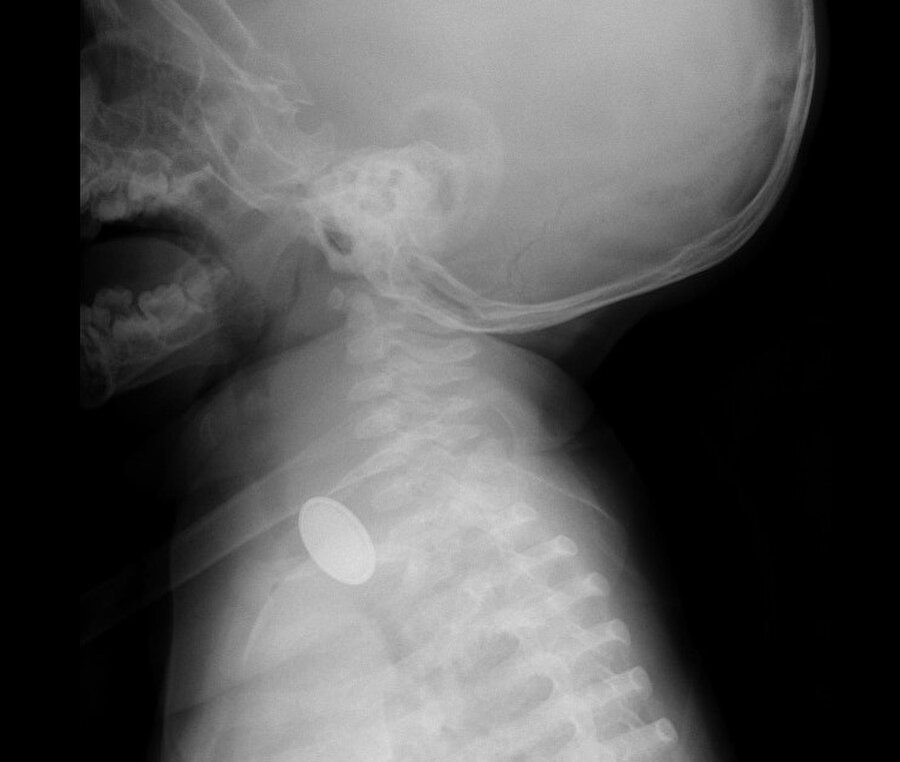

A.Y.Ç.'ye yapılan röntgende, yemek borusunda düğme pil ve lego parçası oyuncağa rastlandı. Kız bebek A.Y.Ç., Kayseri Şehir Hastanesi Çocuk Cerrahisi ve Ürolojisi Anabilim Dalı Başkanı Doç. Dr. Mustafa Erman Dörterler ve ekibi tarafından ameliyata alındı.

Yaklaşık 3 saatlik süren operasyonun ardından A.Y.Ç.'nin yemek borusuna kaçan düğme pil ile lego oyuncak parçası çıkarıldı.